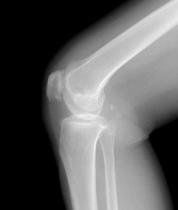

生物體某一部分組織的細胞數目增加,體積擴大。例如皮膚經常受摩擦,上皮和結締組織變厚。如:腰椎增生。